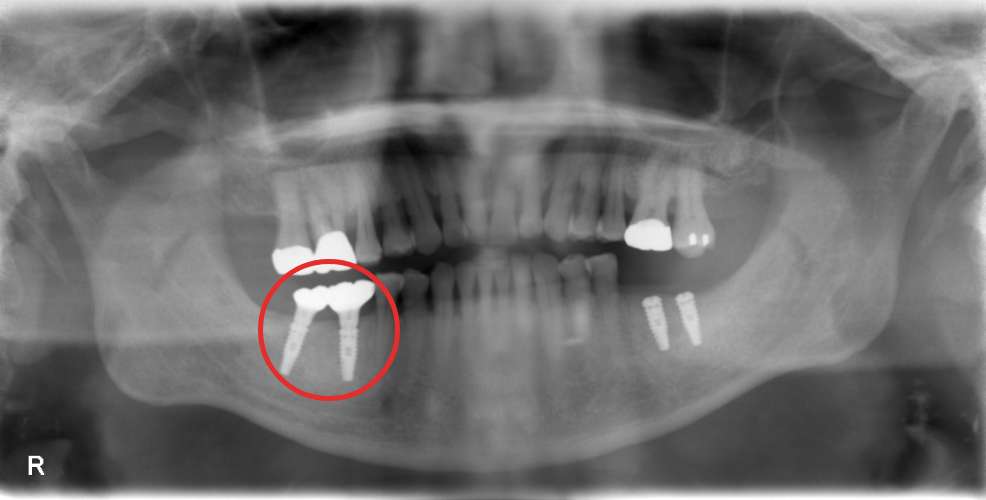

埋入二年後

上部構造装着後のレントゲンと口腔内写真